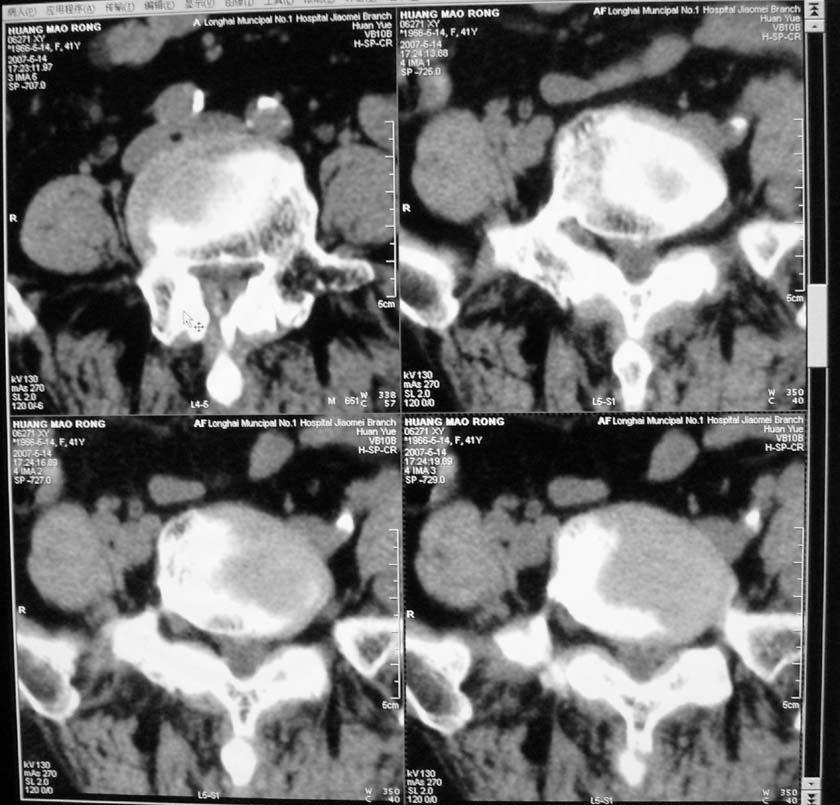

以下是引用jiangjing在2007-5-16 11:05:00的发言:[br]zhichi [br]ct所见:[br]l4-5椎间盘膨出,双侧黄韧带增厚,致使对应椎管变窄,硬膜囊受压.[br][br]l5-s1椎间盘后突,其后硬膜囊受压.l3-4椎间盘未见突出征象.[br]诸椎体边缘及对应椎小关节突骨质增生.腰椎生理曲度正常.[br]腹主动脉壁广泛钙化.[br]印象:[br]1、l4-5椎间盘膨出并双侧黄韧带肥厚及椎管狭窄。[br]2、l5-s1椎间盘突出。[br]3、腰椎及椎小关节退变。